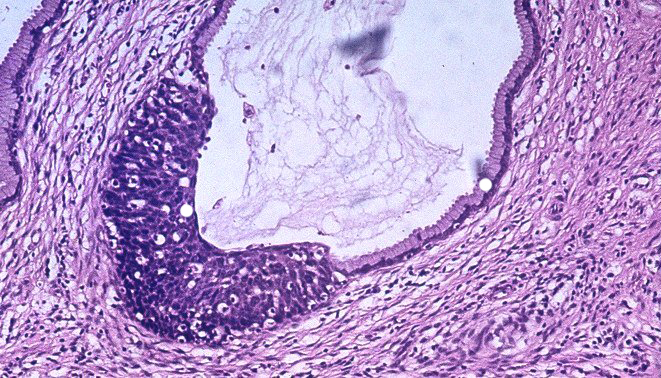

El programa de ciencia, investigación e innovación de Catalunya Informació "La poma de Newton", conducido por Purificación Barceló, se hace eco del estudio liderado por el investigador ICREA Salvador Aznar Benitah, líder del Laboratorio de Células Madre y Cáncer del IRB Barcelona, que identifica las células responsables de iniciar y promover metástasis en varios tipos de tumores humanos.

"Cuando los tumores de pacientes con una predisposición para generar metástasis son estimulados con una dieta rica en grasa o con niveles más altos de palmítico, se vuelven más agresivos. Dependiendo del paciente, un tumor es 10 o 15 veces más metastásico si se le alimenta con niveles más elevados de estas grasas ", explica Salvador Aznar Benitah.